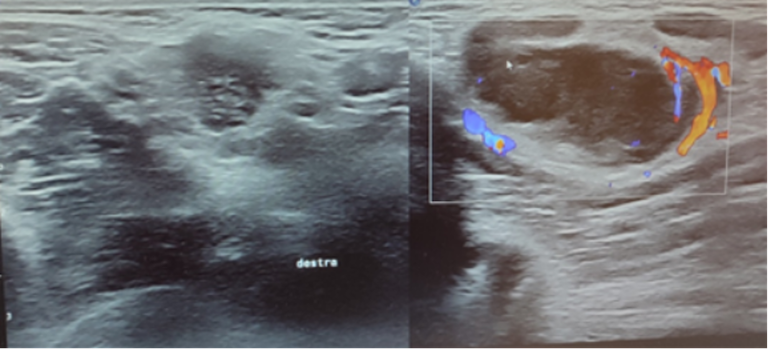

L’ecografia di cute e tessuti molli evidenzia formazione ovalare ipocogena di 2,4x1,2 cm parzialmente colliquata, priva di ilo adiposo e con vascolarizzazione sia periferica che centrale, in prima ipotesi riferibile a linfonodo patologico e concomitante imbibizione edematosa dell’adipe limitrofo con ulteriori piccole formazioni linfonodali con le medesime caratteristiche ecografiche (Figura 1 e Figura 2).